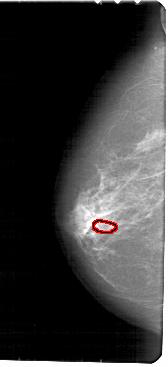

FILE: A_1840_1.LEFT_CC.OVERLAY

TOTAL_ABNORMALITIES 1

ABNORMALITY 1

LESION_TYPE CALCIFICATION TYPE PLEOMORPHIC DISTRIBUTION CLUSTERED

ASSESSMENT 4

SUBTLETY 2

PATHOLOGY BENIGN

TOTAL_OUTLINES 1

BOUNDARY